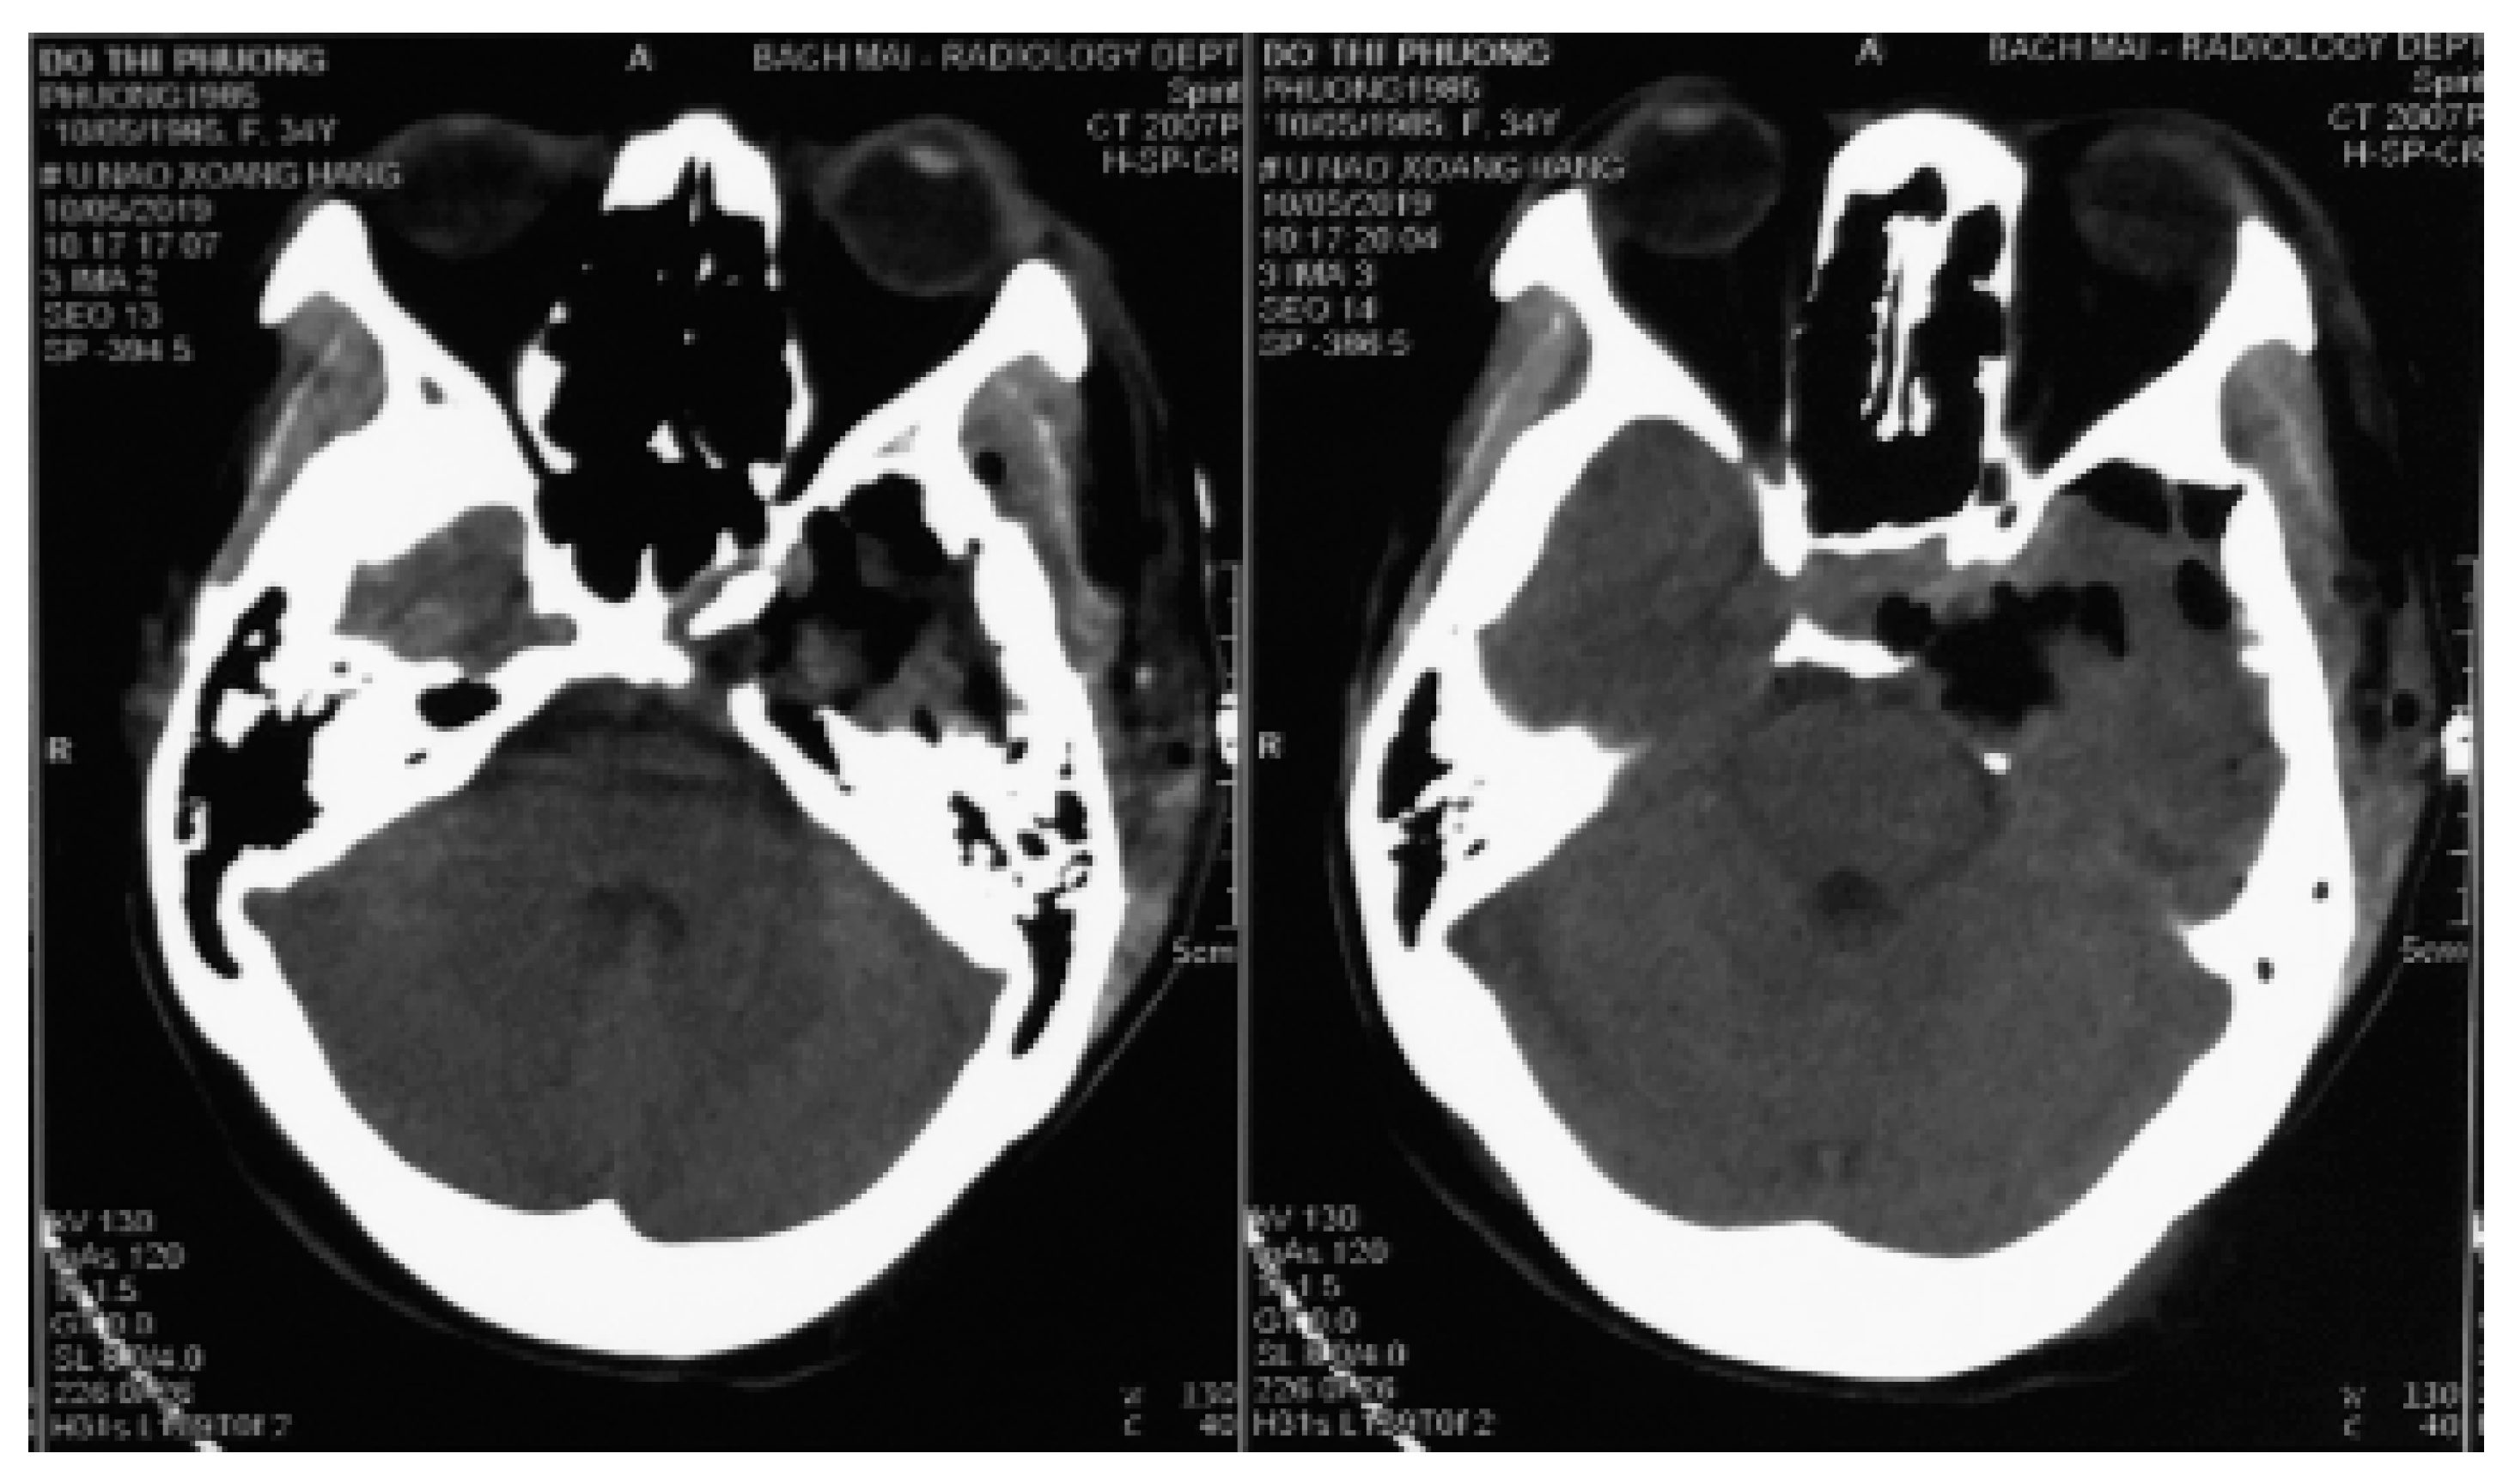

Figure 3.

Two-day postoperative computed tomography scan images.